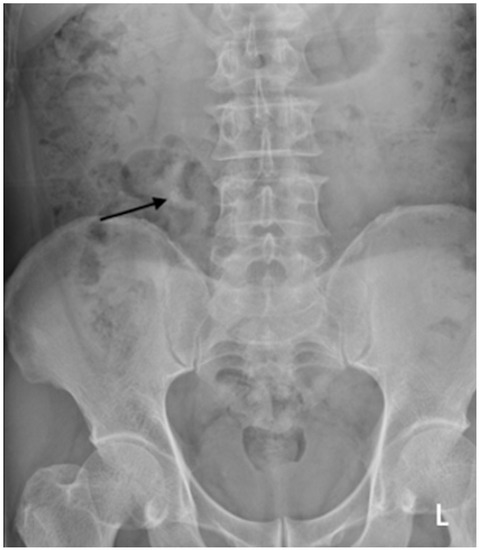

Figure 4. Another example of radiograph categorized as a major discrepancy. A kidney, ureter, and bladder (KUB) radiograph was performed on a 60-year-old man who presented with an acute abdomen. There is an opacity at the course of the right mid ureter with provisional right mid ureteric calculus (black arrow), which the trainee missed.